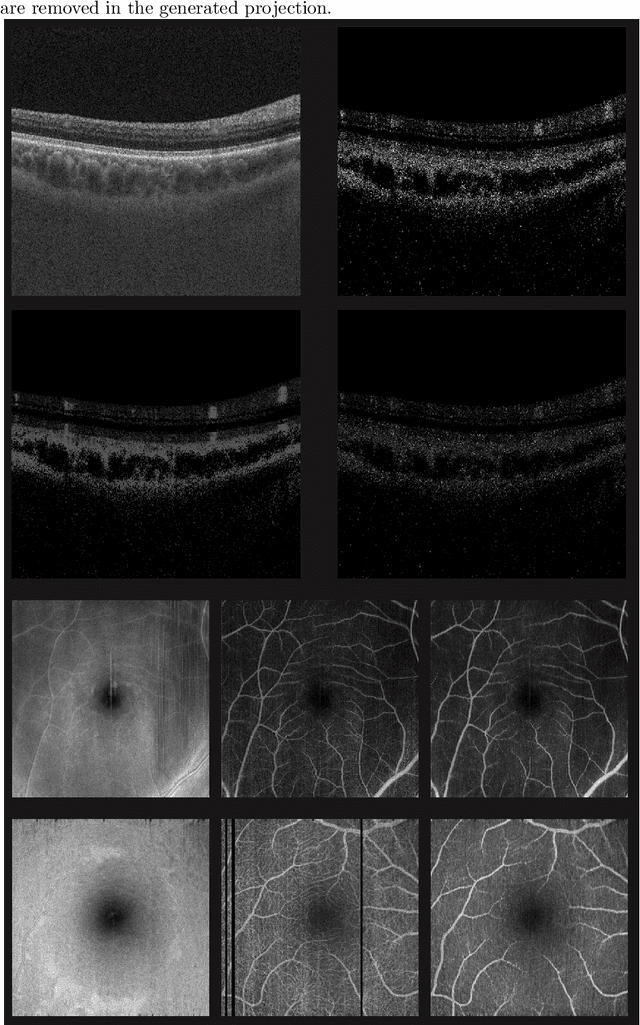

Abstract:Eye movements, blinking and other motion during the acquisition of optical coherence tomography (OCT) can lead to artifacts, when processed to OCT angiography (OCTA) images. Affected scans emerge as high intensity (white) or missing (black) regions, resulting in lost information. The aim of this research is to fill these gaps using a deep generative model for OCT to OCTA image translation relying on a single intact OCT scan. Therefore, a U-Net is trained to extract the angiographic information from OCT patches. At inference, a detection algorithm finds outlier OCTA scans based on their surroundings, which are then replaced by the trained network. We show that generative models can augment the missing scans. The augmented volumes could then be used for 3-D segmentation or increase the diagnostic value.